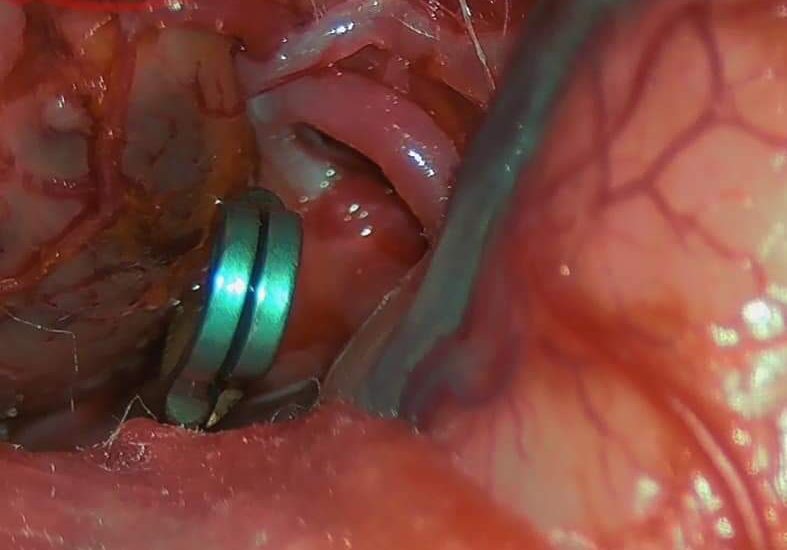

Correction of Congenital sharp angular kyphosis

Female pt 14 yrs, complaining from back pain due to congenital sharp angular kyphosis otherwise there wasn’t any neurological deficit Pre-op X-ray 3D Reconstruction Surgical planing for vertebral column resection of the apical vertebra using surgimap program for accurate correction according to Sagittal balance parameters…